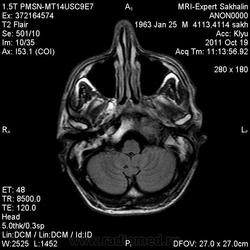

объемное образование ската с распространением на пирвмидку височной кости, область атланто-окципитального сочленения, не выраженно контрастируется- может хордома?-хотя сиггнал по Т2 для нее не типичен ( более характерен гиперинтенсивный МРС) Но ведь возможны вариации?. А КТ не делали?.

Мне тоже показалось, что хордома)))